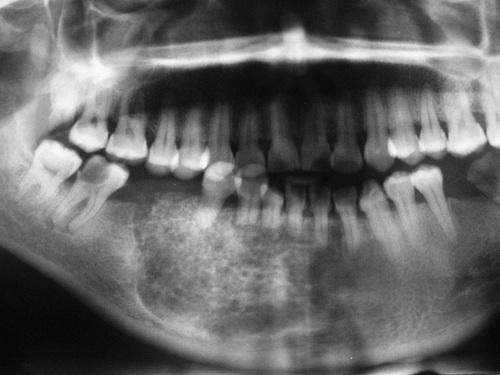

Radiographic Features

- well-defined radiolucent area

- large lesions may appear multilocular

- smooth and often corticated margins

- growth in an anteroposterior direction

- may involve an unerupted tooth (25% to 40%)

This large, multilocular cyst involves most of the ascending ramus and is growing in an anteroposterior direction.

odontogenic keratocyst (OKC)

Large cysts present in the right and left mandibular molar regions, together with a smaller cyst involving the right maxillary canine.

nevoid basal cell carcinoma syndrome